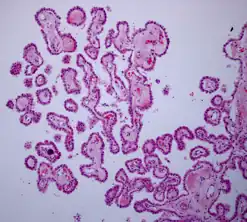

Histologie

Hämatoxylin-Eosin gefärbtes Schnittpräparat. Originalvergrößerung 1:100

Ein Plexus choroideus besteht aus einer Einstülpung der weichen Hirnhaut (Pia mater) und deren epithelialem Überzug aus Zellen der Neuroglia, spezialisierten Ependymzellen, des aus der Wand des embryonalen Neuralrohrs hervorgegangenen Neuroepithels. Dieses einschichtige kubische Epithel des Ependyms weist hier als Lamina choroidea neben Kinozilien auch zahlreiche Mikrovilli an der Oberfläche auf. Darunter befindet sich die aus der Pia mater stammende gefäßreiche Bindegewebsschicht, die Tela chorioidea, mesenchymalen Ursprungs. Über Seitenäste der Arteria carotis interna sowie der Arteria cerebri posterior (caudalis) werden die Adergeflechte mit Blut versorgt.